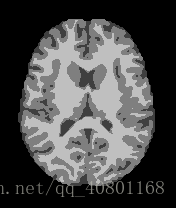

以上三张图片是成年人的大脑核磁共振图像,从左至右分别表示正常人、轻微某病、严重某病。

现在我在用深度学习(BP神经网络、CNN卷积神经网络、迁移学习等)在研究如何分类。